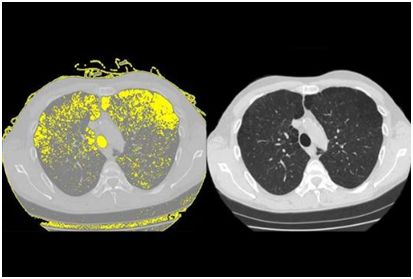

3.HIV 治疗的背后:HIV 如何一步步将患者的肺摧毁!

doi:10.1016/j.celrep.2017.04.026

高达 30%的接受抗逆转录病毒疗法治疗的艾滋病毒患者发展为慢性肺病肺气肿。 Weill Cornell 医学研究人员的新研究发现了一种可能解释为什么会发生肺损伤的机制。

研究人员在“细胞报告”5 月 9 日发表的研究报告中显示,人类免疫缺陷病毒或 HIV 与干细胞结合,称为基底细胞,其转化为其他类型的细胞。该过程重新编程基底细胞,导致它们释放被称为蛋白酶的酶,其可以破坏肺组织并在进行氧气交换的空气囊的壁中戳出孔。

为了进行这项研究,调查人员将正常的人气道基底细胞从健康非吸烟者的肺部收集,并在观察下暴露于艾滋病毒一段时间。将病毒与基底细胞表面结合并重新编程,以开始产生可以分解蛋白质并破坏组织的酶或蛋白酶,称为金属蛋白酶 -9。因为研究人员知道肺气肿是气道疾病,这一发现表明,当基底细胞呈现称为“破坏性表型”的晶型时,他们开始在健康组织中消失,这会及时得导致肺气肿。